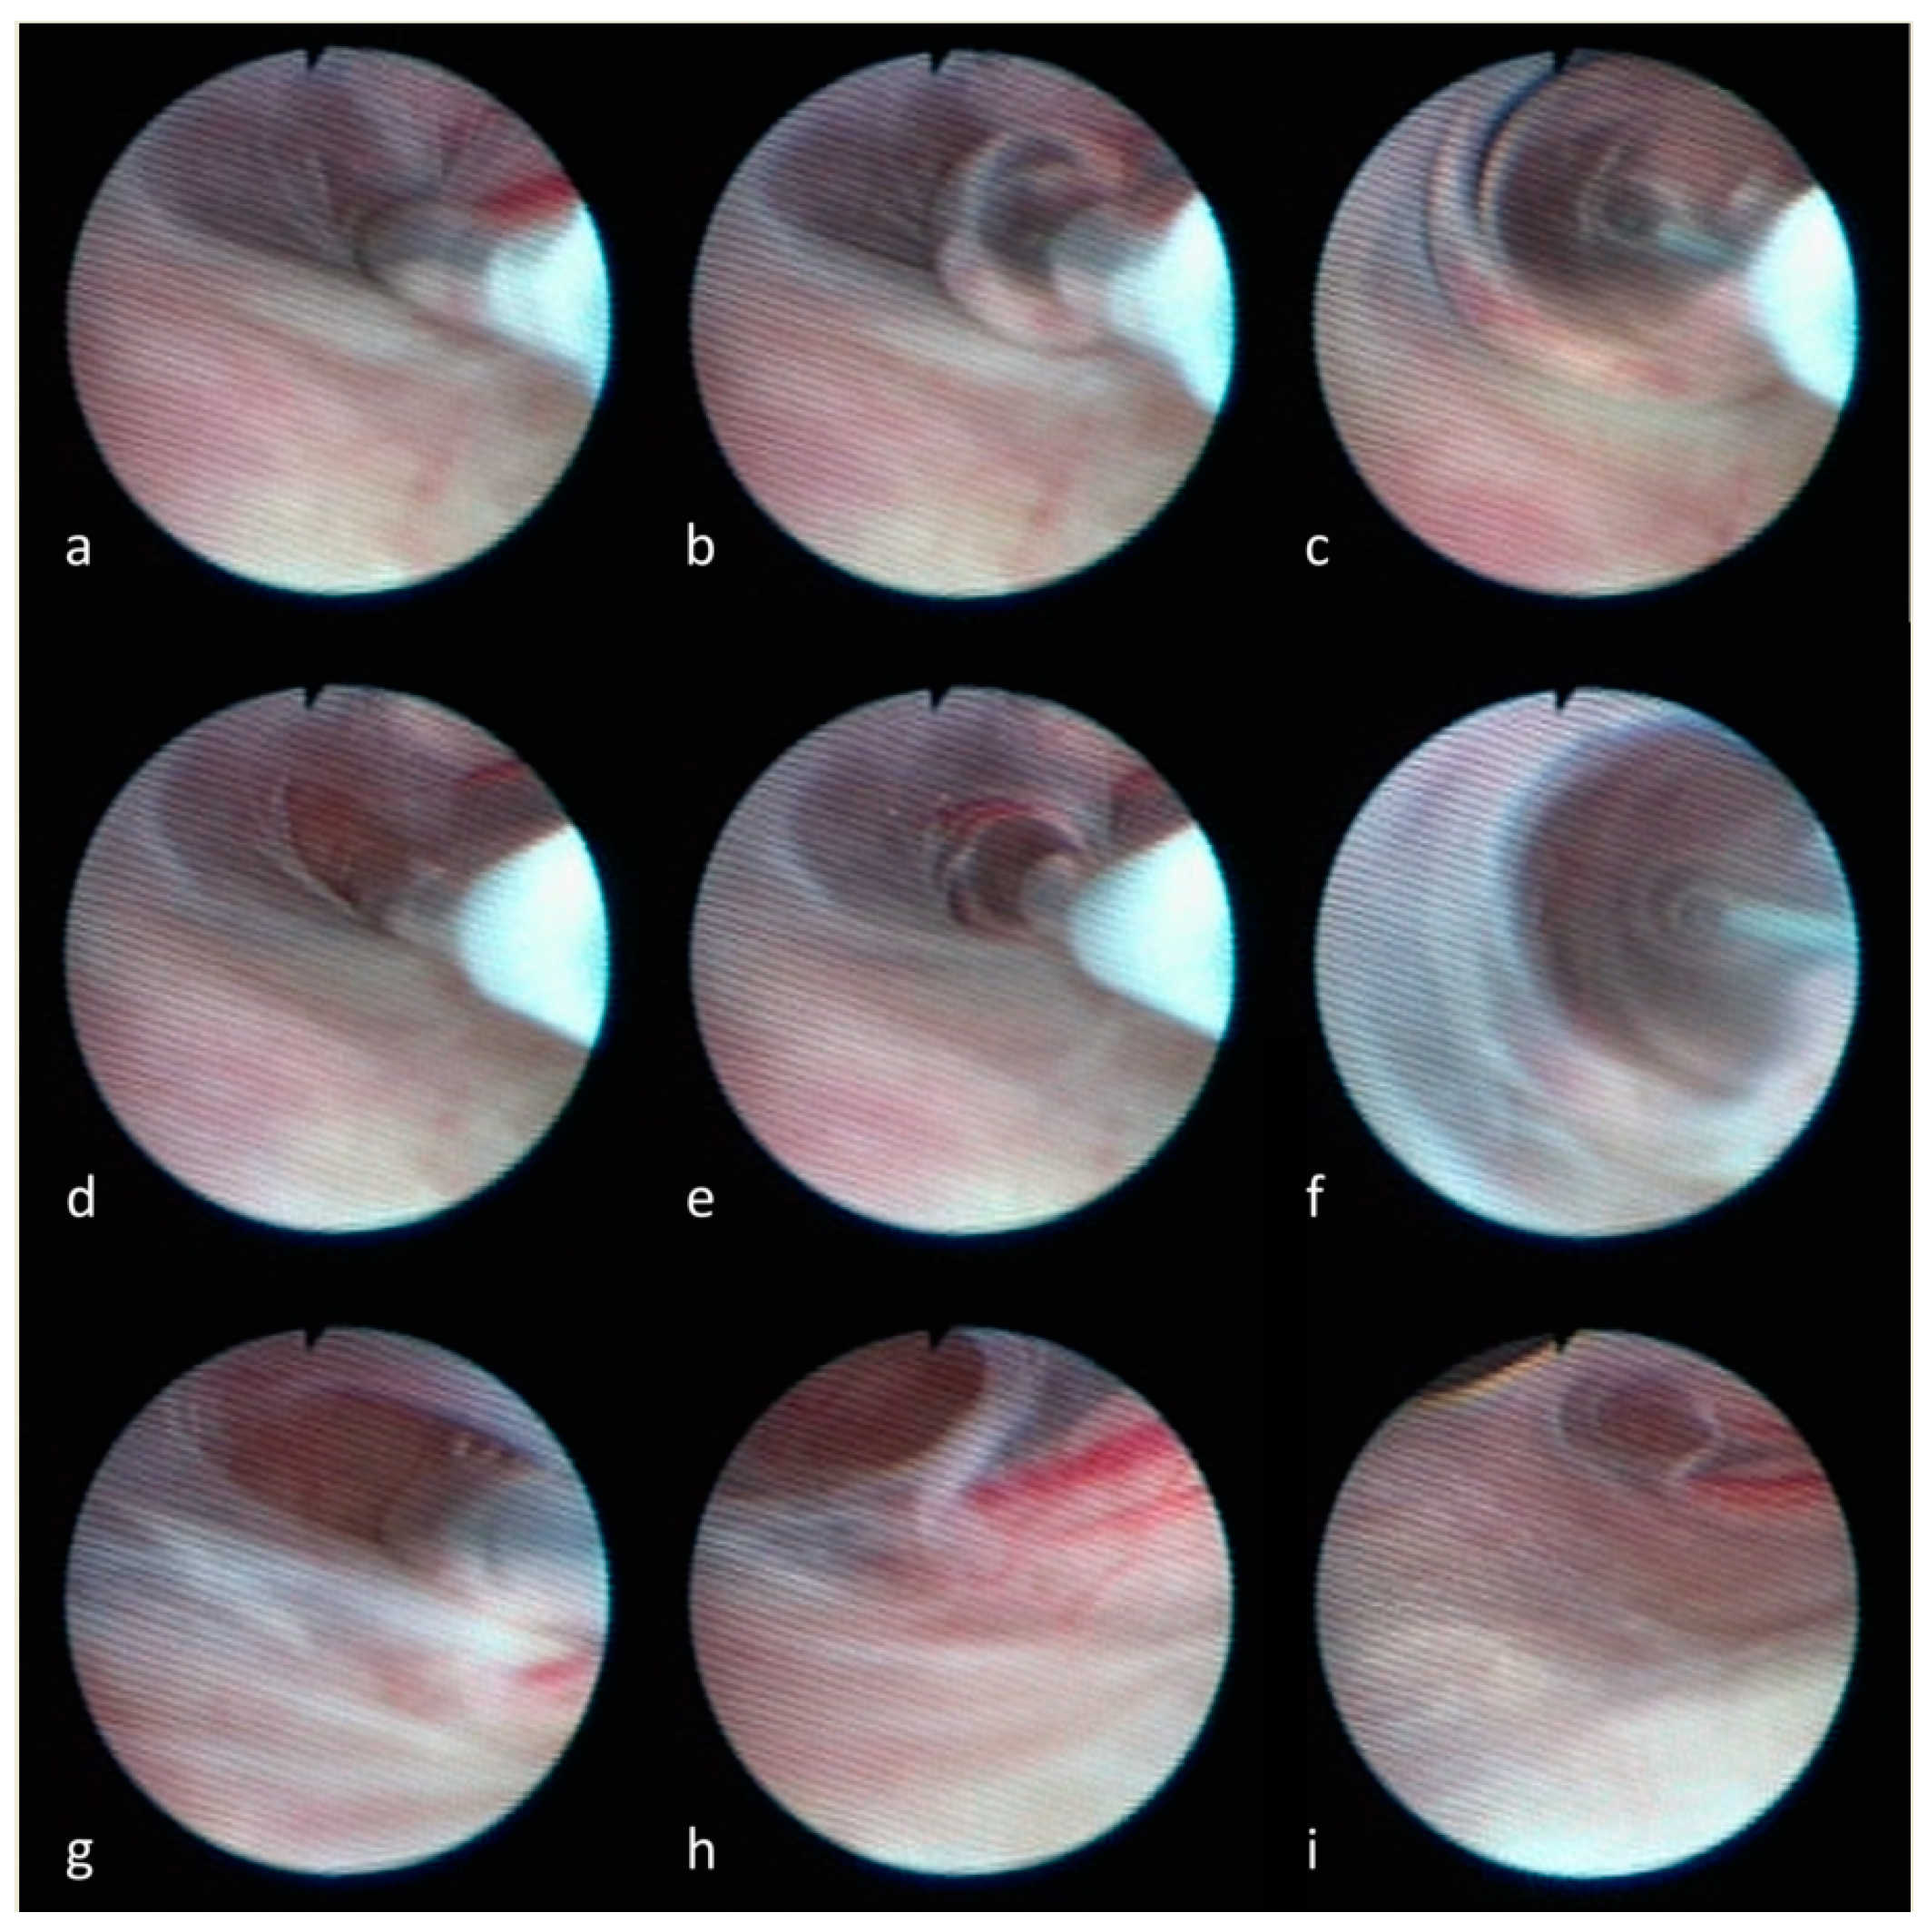

- Luchtmann, M.; Klammer, A.; Iova, M.A.; Roth, A.; Mawrin, C.; Warnke, J.P. Combined endoscopic and microsurgical treatment of Tarlov cysts. Interdiscip. Neurosurg. 2023, 36, 101925. [Google Scholar] [CrossRef]